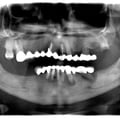

Імплантація 16,17,18 без врахування жодних правил оклюзії та знань в імплантології